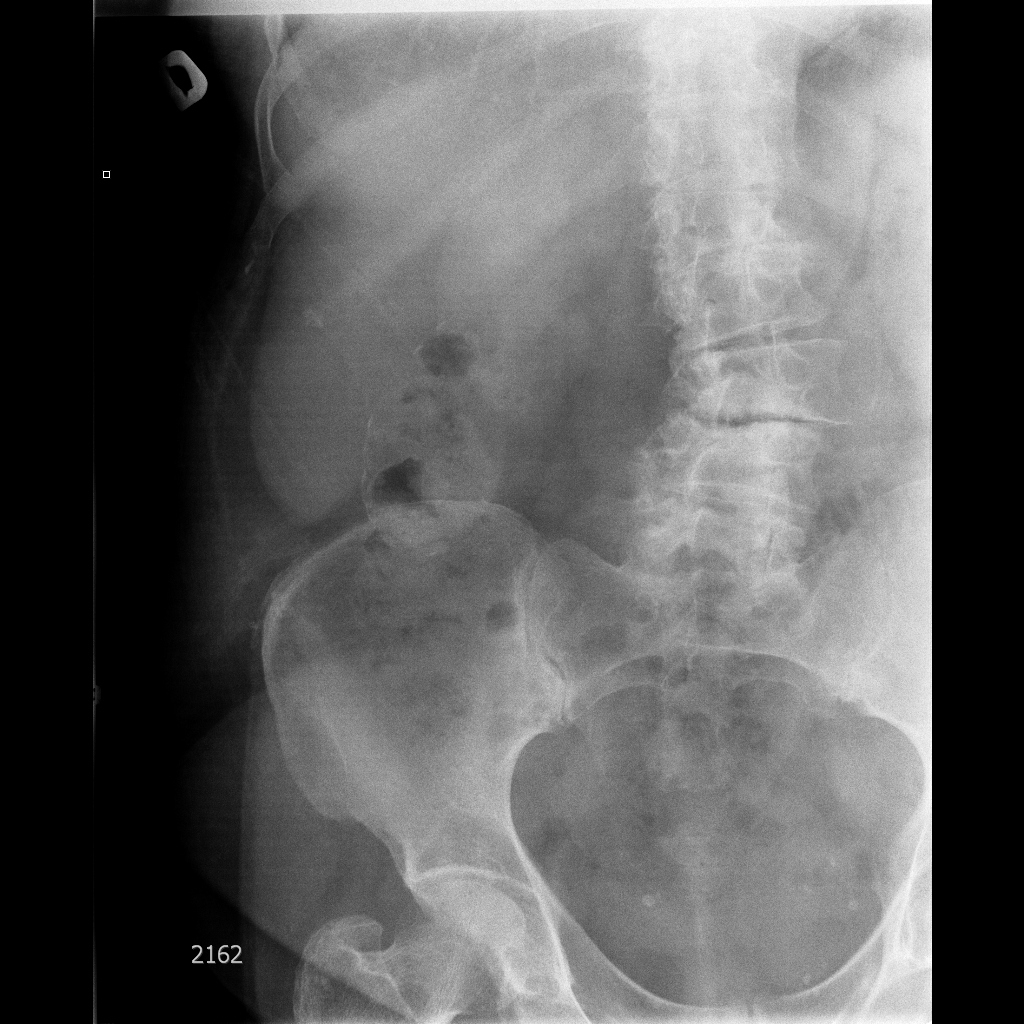

Фарфоровый желчный пузырь (Porcelain gallbladder)

Женщина средних лет без жалоб на здоровье.

Еще случай.

Бабушка из отделения сестринского ухода, без жалоб на боли в животе. Лаб. анализы не изменены.

Если кальциноз стенки полный и содержимое пузыря осмотру не доступно, то есть показания к проведению КТ-МРТ. Если стенки инкрустированы частично (как в представленных случаях) и можно оценить характер содержимого и структуру стенок, то можно ограничиться только УЗИ. Далее, если есть подозрение на опухоль то пациента направляют к онкологу, а он сам определяет дальнейшую тактику.

Это форма хронического холецистита с кальцификацией стенки ЖП. Термин "фарфоровый" отражает голубоватый оттенок и хрупкую консистенцию ЖП. У мужчин возникает в 5 раз чаще. Кальцификация стенки представляет собой либо непрерывную кальцификацию мышечного слоя, либо прерывистую кальцификацию слизистой и подслизистой. У таких больных высока частота возникновения рака ЖП (11-33%) Каждый раз, когда при УЗИ имеется подозрение на фарфоровый ЖП, для подтверждения диагноза и оценки степени злокачественности проводят КТ